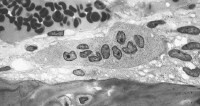

Osteoclasts, derived from mesenchymal cells, are responsible for bone resorption, whereas osteoblasts, from hematopoietic precursors, are responsible for bone formation (see the images below). The 2 types of cells are dependent on each other for production and linked in the process of bone remodeling. Osteoblasts not only secrete and mineralize osteoid but also appear to control the bone resorption carried out by osteoclasts. Osteocytes, which are terminally differentiated osteoblasts embedded in mineralized bone, direct the timing and location of bone remodeling. In osteoporosis, the coupling mechanism between osteoclasts and osteoblasts is thought to be unable to keep up with the constant microtrauma to trabecular bone. Osteoclasts require weeks to resorb bone, whereas osteoblasts need months to produce new bone. Therefore, any process that increases the rate of bone remodeling results in net bone loss over time.[19]